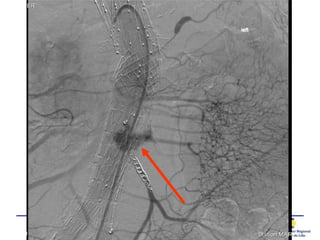

Ponction translombaire –

embolisation directe

• Bon résultat de la ponction lombaire

• Comme alternative en cas d’échec de ttt

transartériel